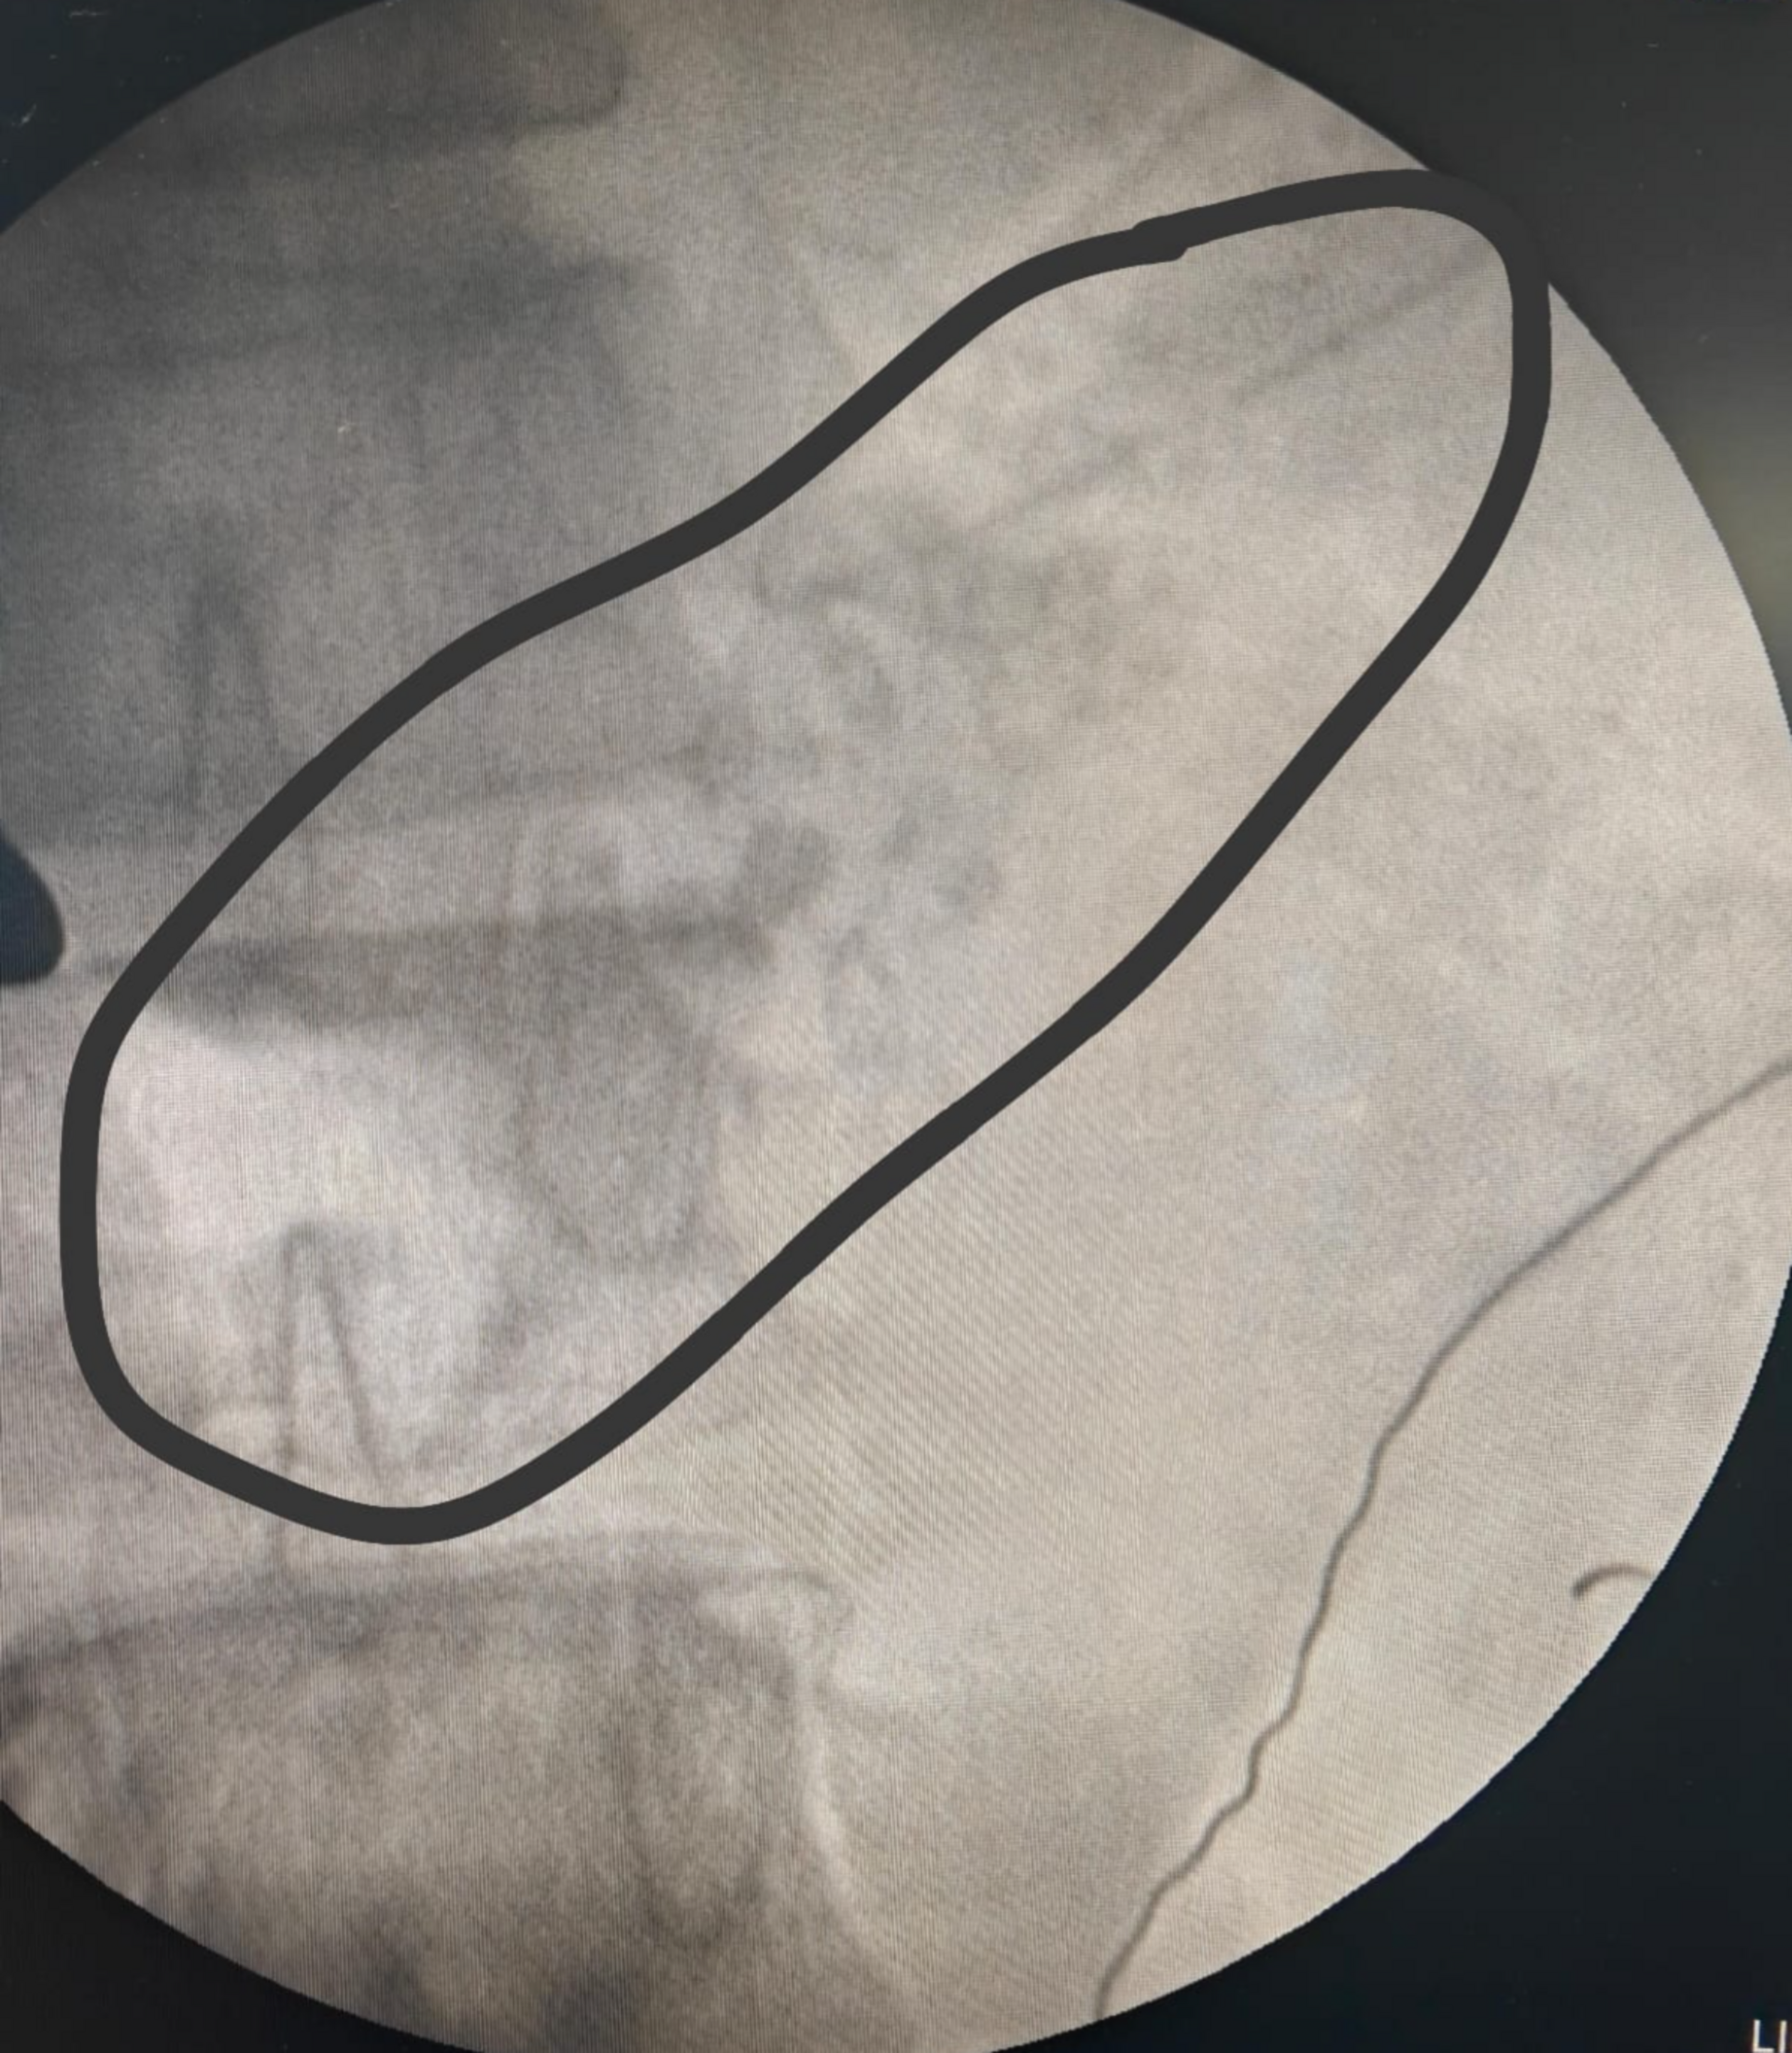

Expert Management of Bleeding Duodenal Ulcer: Insights from Dr. Harshal Rajekar

Dr. Harshal Rajekar, an esteemed Hepatobiliary, GI, and Liver Transplant Surgeon, recently treated a challenging case of a bleeding duodenal ulcer. Fo...